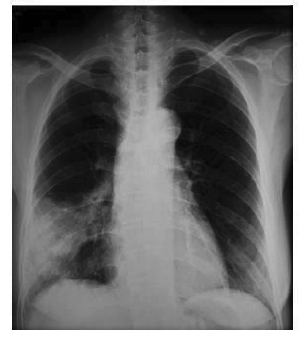

Madam L is a 58 year old housewife that suffered from end stage renal failure (ESRF) due to chronic glomerulonephritis with haemodialysis in Queen Elizabeth Hospital (QEH) since 2001. She underwent cadaveric renal transplant in mainland China in August 2002 and was put on immunosuppressive treatment that included tacrolimus, prednisolone and azathioprine. She complained of cough and weight loss for 2 months since January 2006. Chest x-ray (CXR) upon admission revealed right lower lobe (RLL) consolidation (Figure 1). Sputum specimens for bacterial culture, cytology, acid-fast bacilli (AFB) staining and culture were all negative. Computed tomography (CT) of thorax revealed RLL consolidation with an area of necrosis. Blood specimens for bacterial cultures, cytomegalovirus antigen (CMV pp65), serum Galactomannan, cryptococcal antigen and Burkholderia pseudomallei IgG/IgM (ELISA) were all negative.

Figure 1. CXR on admission showing right lower lobe consolidation